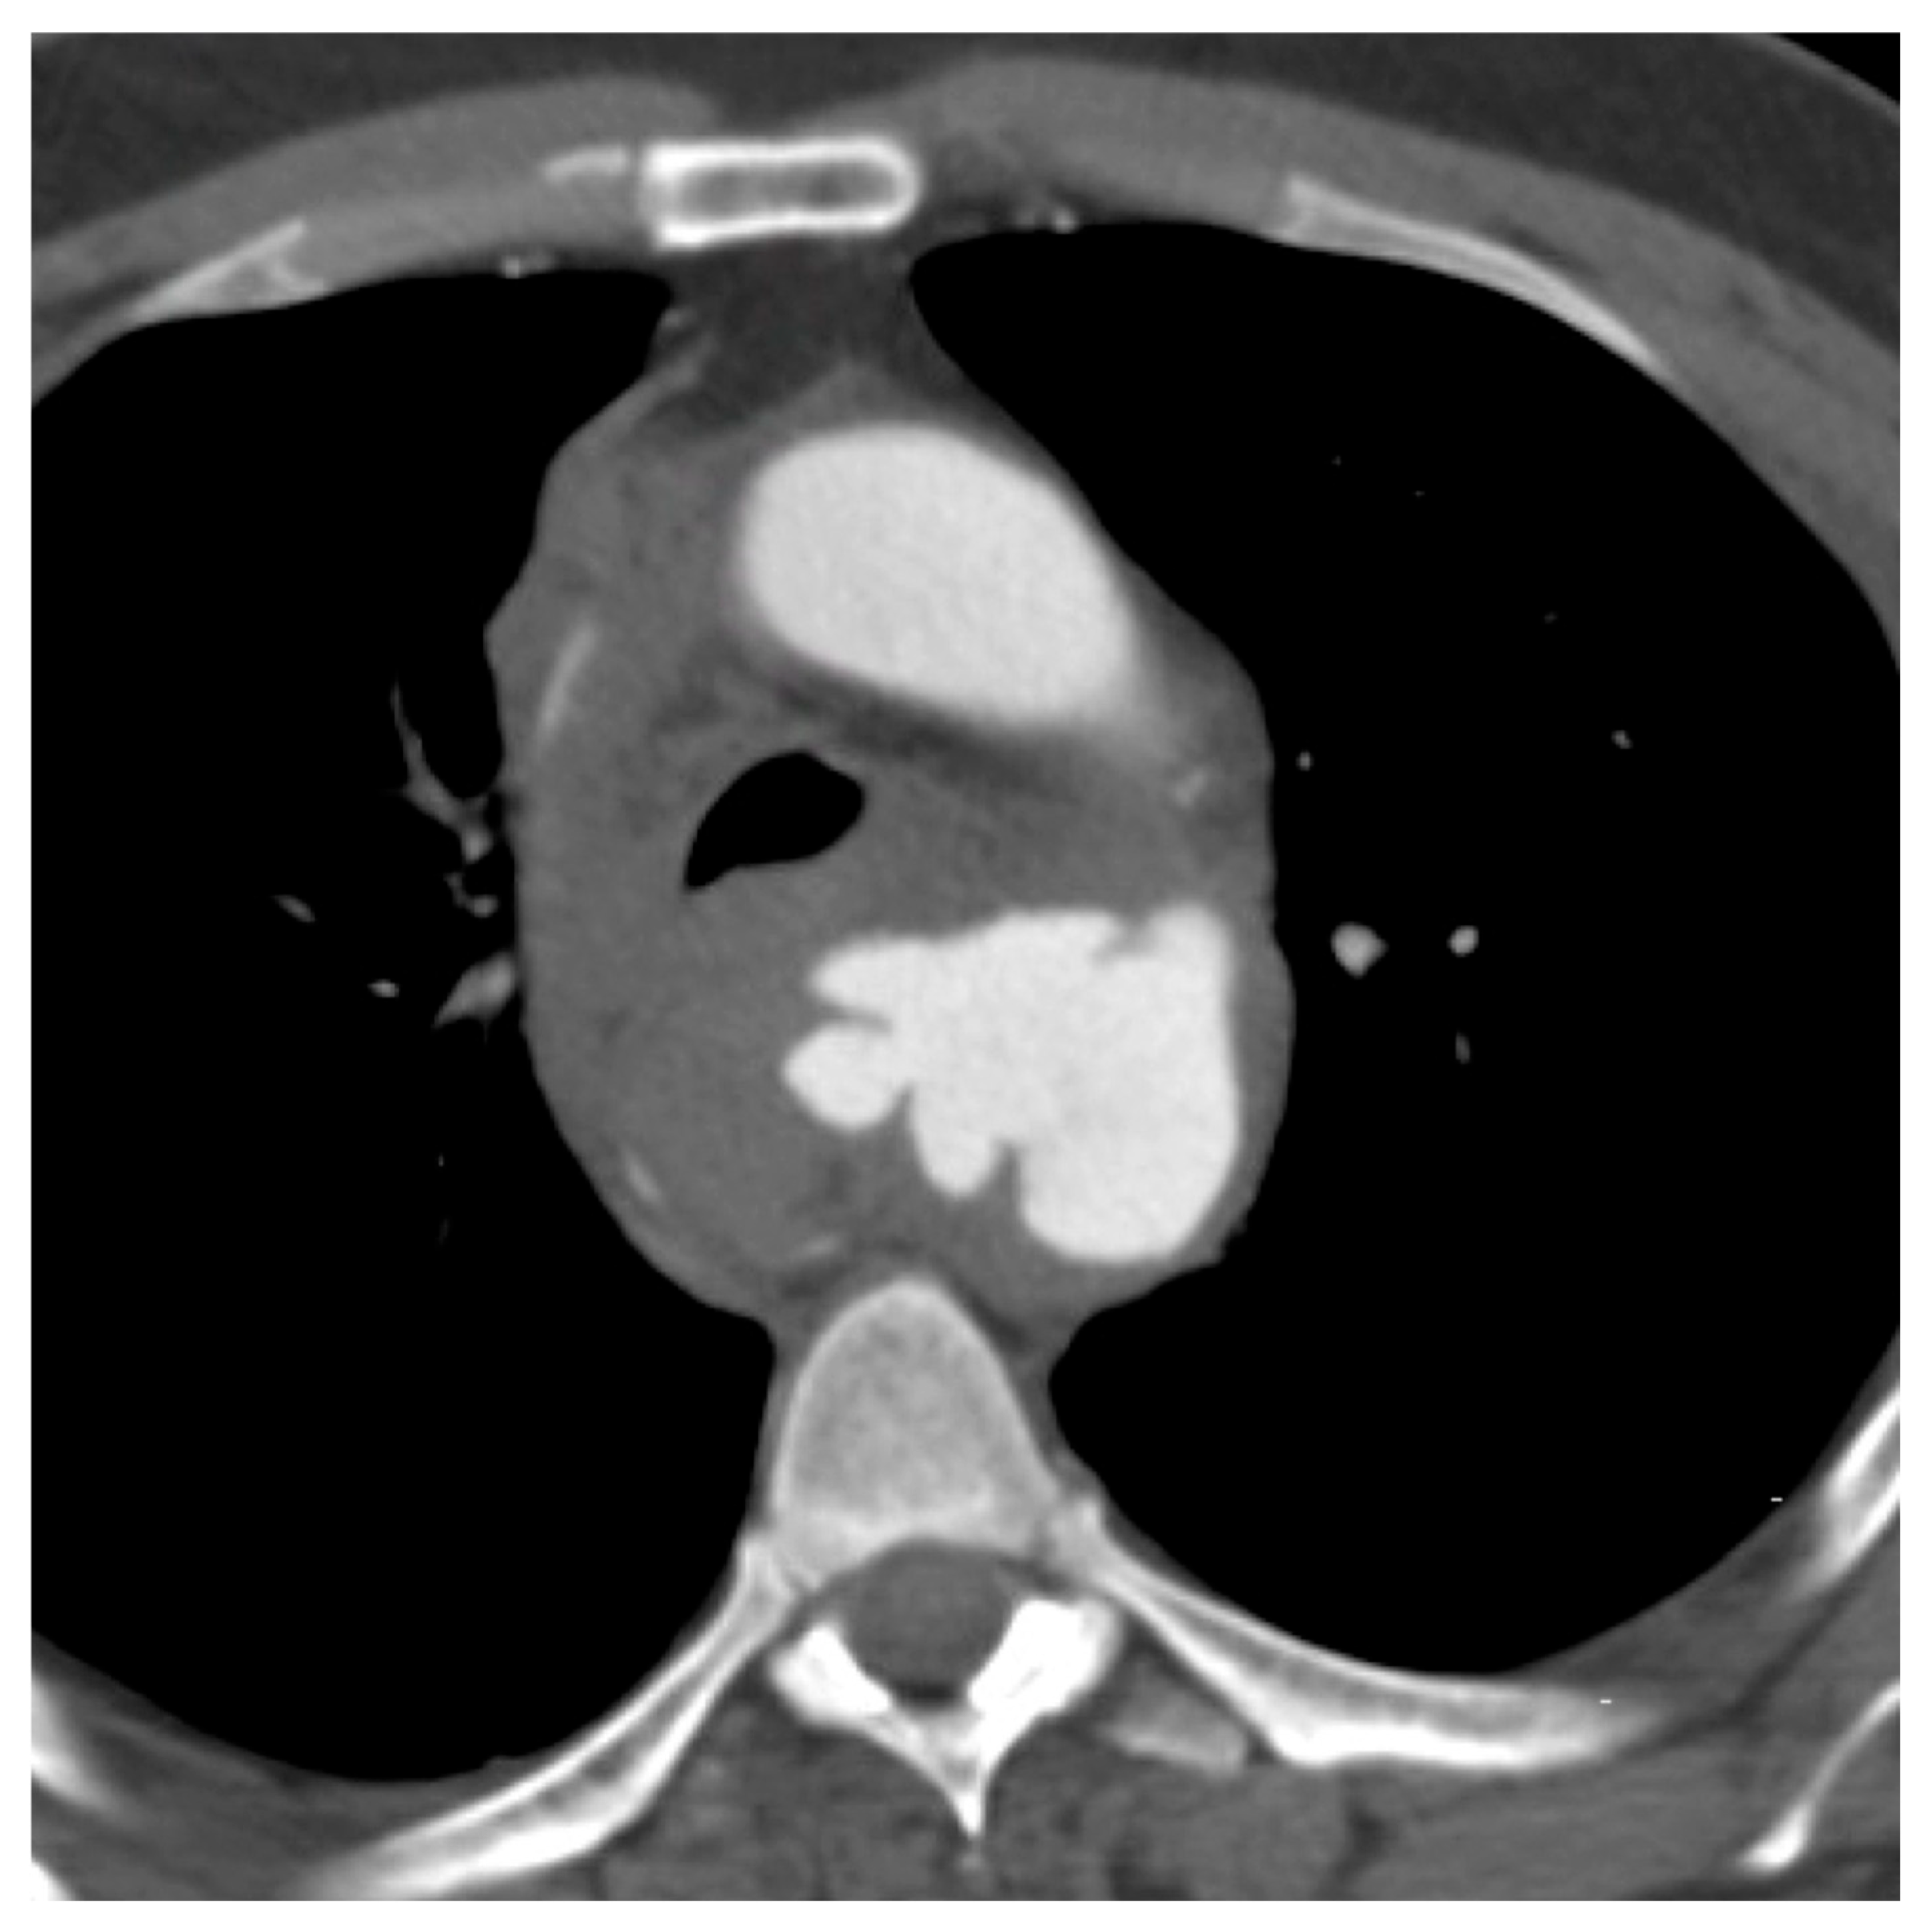

| 3 (pseudoaneurysm) | 22 (58%) |